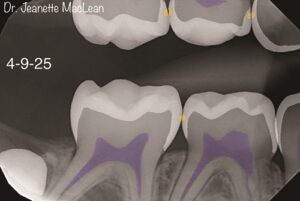

In the January 2026 issue of Dentaltown magazine, Dr. Jeanette MacLean describe how AI technology can be used to diagnose and treat incipient caries lesions with minimal interventions like SDF and remineralization.